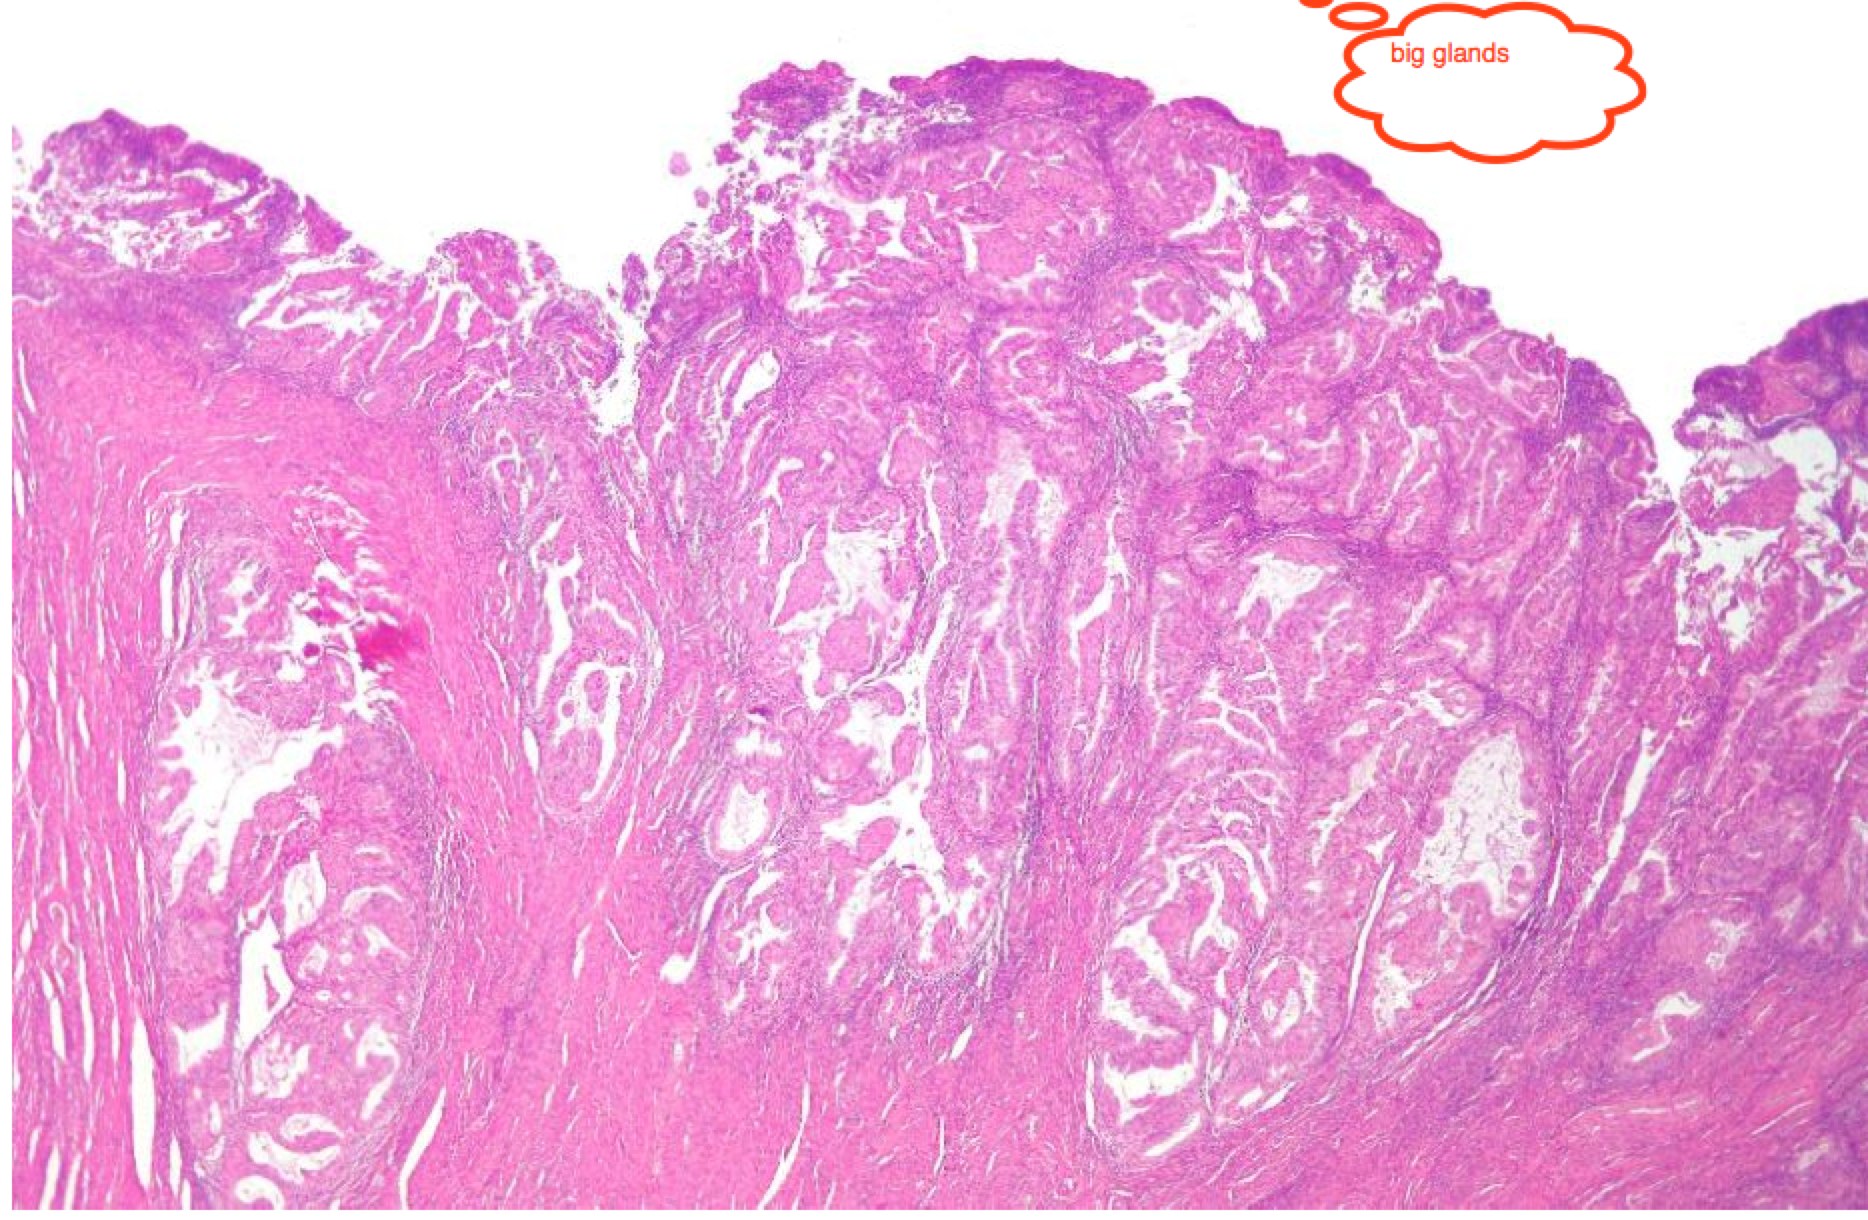

The majority of cases are endometrioid, which is divided into low, intermediate and high grades (Grade I-III). These are commonly low grade, estrogen responsive, and are much more common. Papillary serous and clear cell cancers are much more agressive and should be considered high risk disease.

More recently, histopathlogists have divided the two groups into "Type I" and "Type II" cancers. Type II are the serous and clear cell cancers, which are generally more agressive and much less common than endometriod cancers.

Endometrioid: Big well structured glandsPapillary serous with sheets of cells between disorganized glands